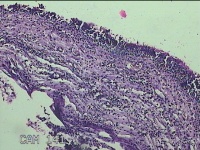

双侧鼻腔新生物

性别

男

年龄

55岁

临床诊断

1.慢性鼻窦炎 2.鼻腔新生物 3.鼻中隔偏曲 4.过敏性鼻炎

一般病史

反复鼻塞、脓涕伴嗅觉减退20余年。

标本名称

大体所见

灰白粉红色肿物2.3x1.3x0.3cm两个,表面光滑,切开肿物呈囊性,囊内充满大量灰白色角化物,囊壁厚0.1cm。

所提供图片不具有诊断价值,炎性病变可能。